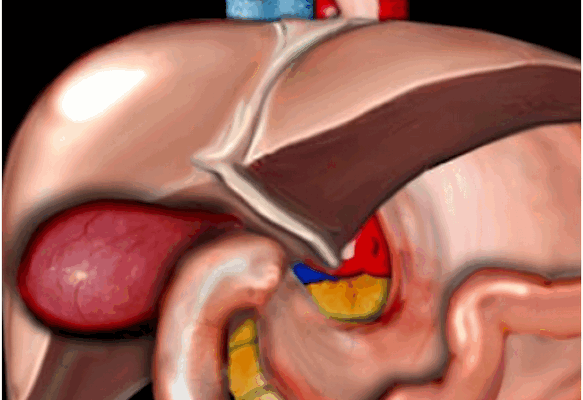

Схематичная патология. На данном рисунке продемонстрирован растянутый и гиперемичный желчный пузырь. Данные изменения встречаются при калькулезном холецистите, обусловленные обструкцией камнем желчного протока или шейки желчного пузыря.

УЗИ признаки калькулезного холецистита.